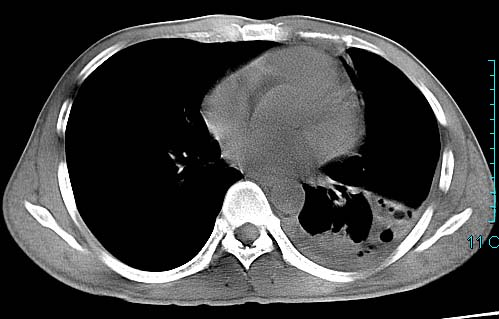

以下是引用ctkz987在2006-3-28 13:04:00的发言:[br]左侧胸腔积液穿刺后多发气液平(多房性),结合临床有高热不除外合并感染。

以下是引用qian在2006-3-28 14:32:00的发言:[br]左肺下叶大片状阴影,密度不均,见有条片影和空洞及气液平,少量胸腔积液伴有胸膜增厚,从图像看积液密度比水的密度高,结合病史,考虑左下肺化脓性炎症伴有脓胸。

以下是引用wawaquan在2006-3-28 22:25:00的发言:[br]左上肺舌段多发斑片影。结合“男24y咳嗽咳痰气促伴高热(38.5--39.5)20多天”及穿刺史,[br]考虑1 左下肺化脓性炎症;2脓胸。

以下是引用乡医在2006-3-28 18:37:00的发言:[br]左侧多发液气平面结合患者男24y咳嗽咳痰气促伴高热(38.5--39.5)20多天,查胸水:ldh239.3,总蛋白59.19,tb-ab阴性,利凡它试验+,红c2.7*109,白c1.08*109,分类淋巴92%分叶8%,考虑1脓胸2肺隔离征感染